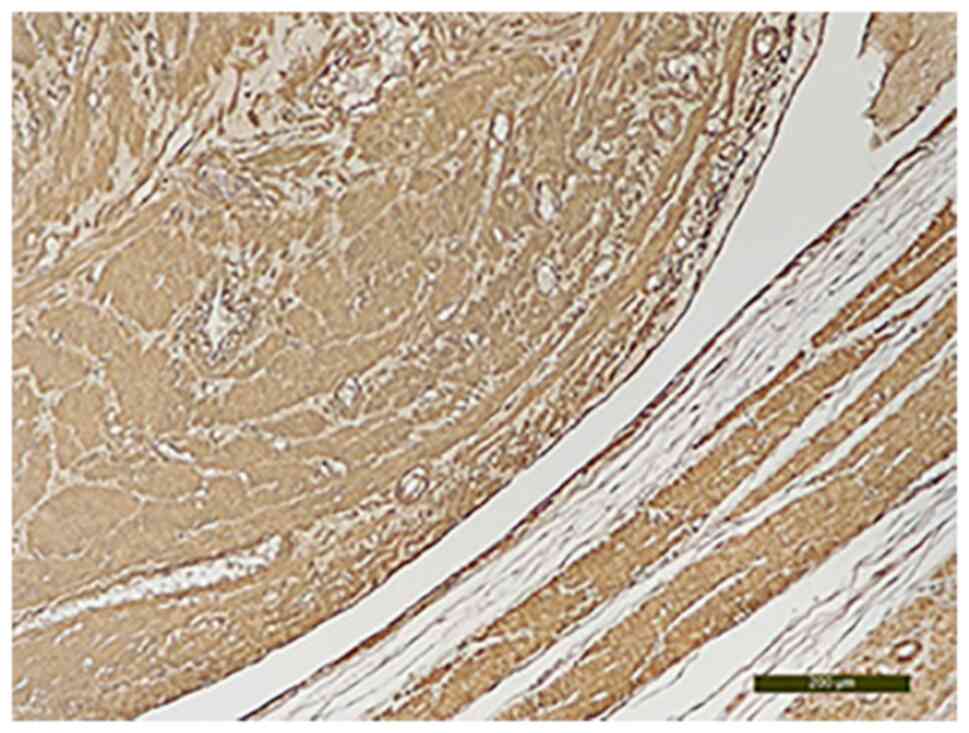

The CD34 analysis established its intravascular origin (Fig. 8). The immunohistochemical evaluation revealed that the area of the tumor that had intravascular development was positive for estrogen receptors (Fig. 9) and for the smooth muscle actin marker (Fig. 10). Intravascular origin was evaluated using a CD34 marker for endothelial cells. Incubation was with the primary antibody (anti-CD34) by applying the optimal dilution in a humid chamber at 4˚C, overnight. The anatomopathological diagnosis was confirmed by two experienced pathologists.

Figure 9

Estrogen receptors highly positive in intravascular leiomyomatous tumor (anti ER; magnification, x10).